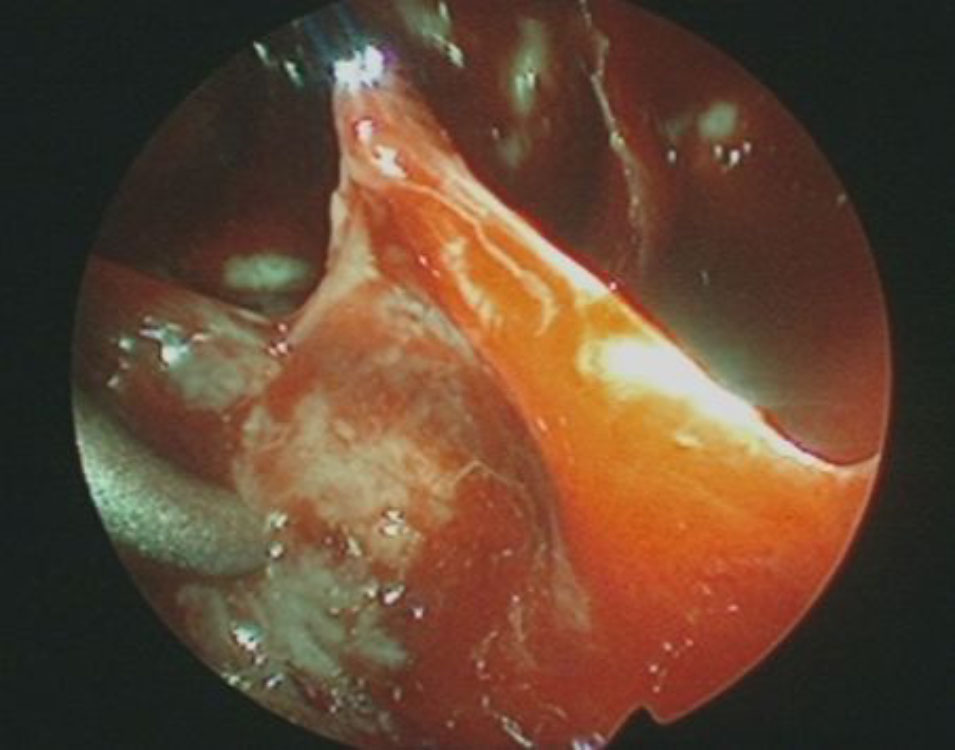

頭蓋内腫瘍摘出術

No.’25_103 摘出 前

No.’25_103  摘出 中